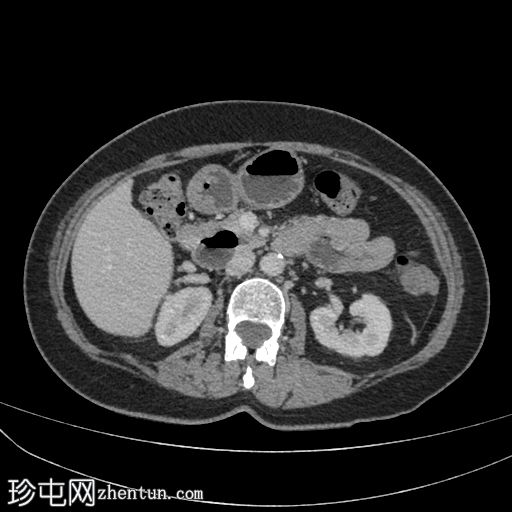

CT

腹部CT显示十二指肠第二段和第三段可见气液平面,无并发症。未见其他异常。

病例讨论

这是十二指肠憩室的典型

影像

学表现和位置;通常无症状。

需注意的并发症包括穿孔、胆管梗阻和胰腺炎。